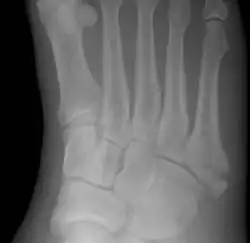

Jones fracture as seen on Xray

Diagnostic X-rays include anteroposterior, oblique, and lateral views and should be made with the foot in full flexion.